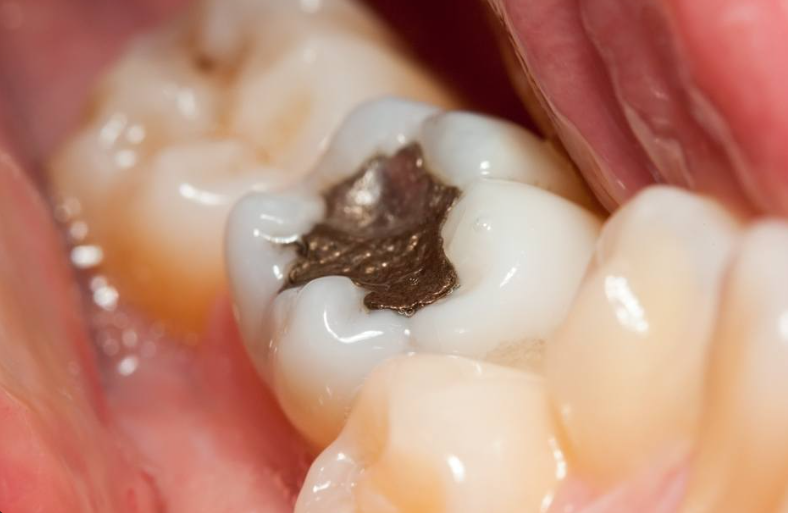

Say goodbye to dark, unsightly fillings and hello to a brighter, healthier smile! White fillings are a modern, mercury-free alternative to traditional silver (amalgam) fillings. Not only do they offer excellent bond strength and durability comparable to metal fillings, but they also enhance the aesthetics of your teeth. Whether you’re dealing with a leaky metal filling or simply want a more natural look, replacing old amalgam fillings with white fillings is a safe and effective solution.